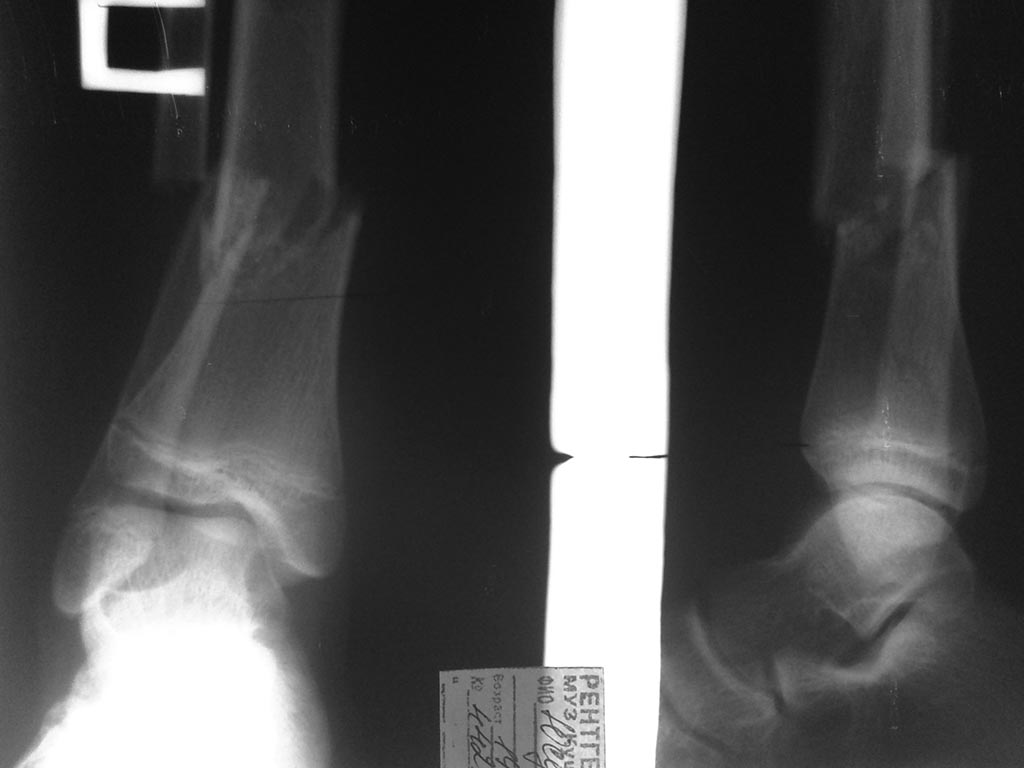

[Ortho] Низкий перелом голени: БИОС ?

Уважаемые коллеги!Прошу разъяснить ситуацию-каким способом вы

предпочитаете синтезировать подобные переломы?

В нашем отделении даются рекомендации оперировать подобные переломы

открыто -LCP.Аргумент против БИОС - возможная нестабильностьучитывая

короткий дистальный фрагмент.С какими проблемами можно столкнуться в

ходе имплантации штифта , реабилитационном периоде? Спасибо за внимание!